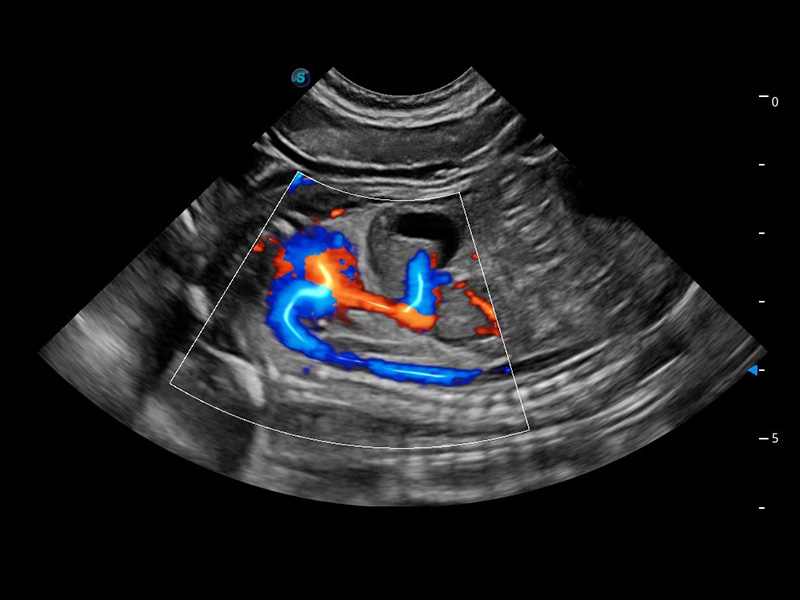

4T血流成像 微察秋毫

融合不同血流成像技术的优势,即可以提升血流成束性,同时可提高血流的视觉敏感性。

Bright Flow 立体血流成像

在传统二维血流成像的基础上,呈现血流的立体感,具有动感的生命力之美。精确区分不同血管的空间关系,提高了血流的视觉敏感性。

优异的基础图像

(犬)四腔心血流

(猫)髂动脉血流频谱